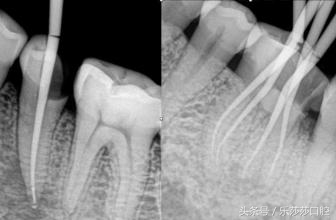

如图所示,我们的牙齿可以用「坚强的外表,柔弱的内心」来形容,最外面一层「牙釉质」非常坚硬耐磨,硬度堪比金刚石,但是坚强外表的里面是一个「空心」,称作牙髓腔和根管,里面分布着许多的血管,神经等。当里面「柔弱的内心」受到细菌的破坏发炎时,会造成牙髓炎、根尖周炎,从而牙齿会敏感,疼痛,尤其夜晚疼痛会加重。而牙髓一旦发炎就不能再恢复了,必须进行根管治疗,才能彻底治愈牙病。